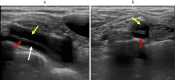

Right subclavian artery dissection was detected in a 78-year-old female victim of the Kumamoto earthquake during a carotid artery ultrasound examination. She was subsequently taken to hospital and diagnosed with localized subclavian artery dissection (LSAD) by contrast-enhanced computed tomography. There have been no previous reports of LSAD detected at a medical checkup. LSAD may progress and become severe, even in asymptomatic patients or patients with mild symptoms, and careful long-term follow-up is therefore required in all patients diagnosed with LSAD.